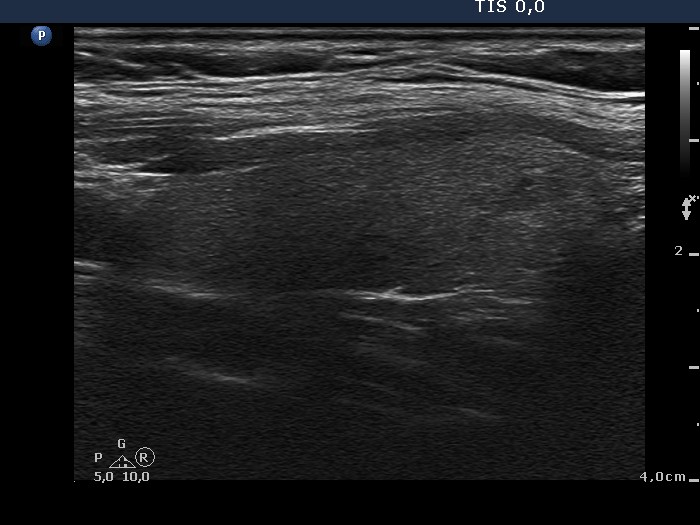

Benign nodular hyperplasia - Case 59. (ultrasonographic picture 8)

Left lobe, longitudinal view.